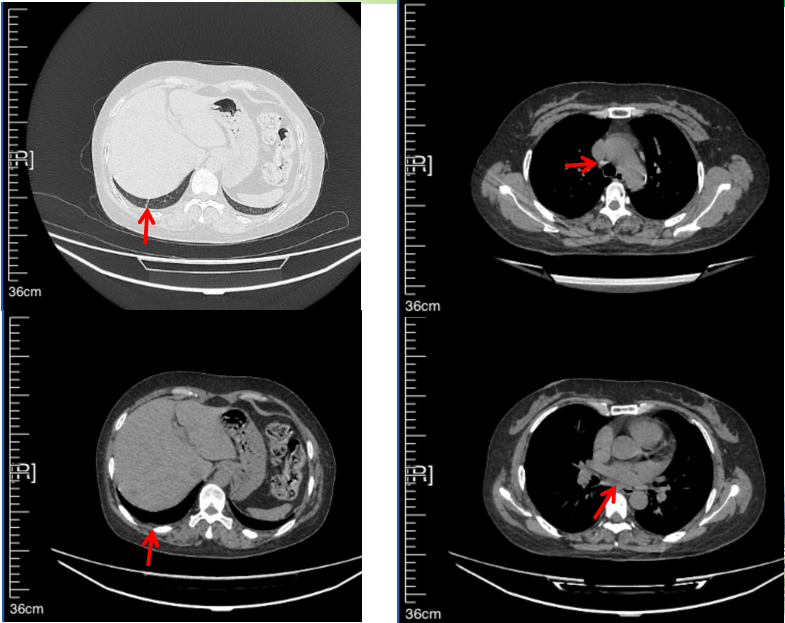

治疗经过:2023年3月27日始行恩沙替尼靶向治疗至今,最佳疗效为PR,末次评效为维持PR。期间出现轻度肝功能异常(DILI 1级),对症处理后好转。截止目前PFS为26个月。

2024年6月复查PR(最佳疗效)

2024年12月复查维持PR